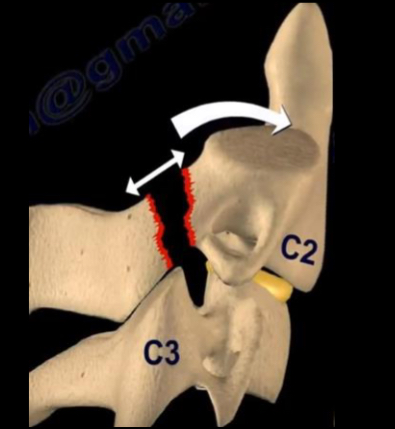

what is a hangman’s fracture?

Historically due to hanging but also seen

in RTC’s where the face strikes the

windscreen forcing the neck into

hyperextension.

• Hyperextension and distraction results

in bilateral fractures through the pedicles

of the axis (C2), with anterior dislocation

of the body and subsequent tearing of

the spinal cord